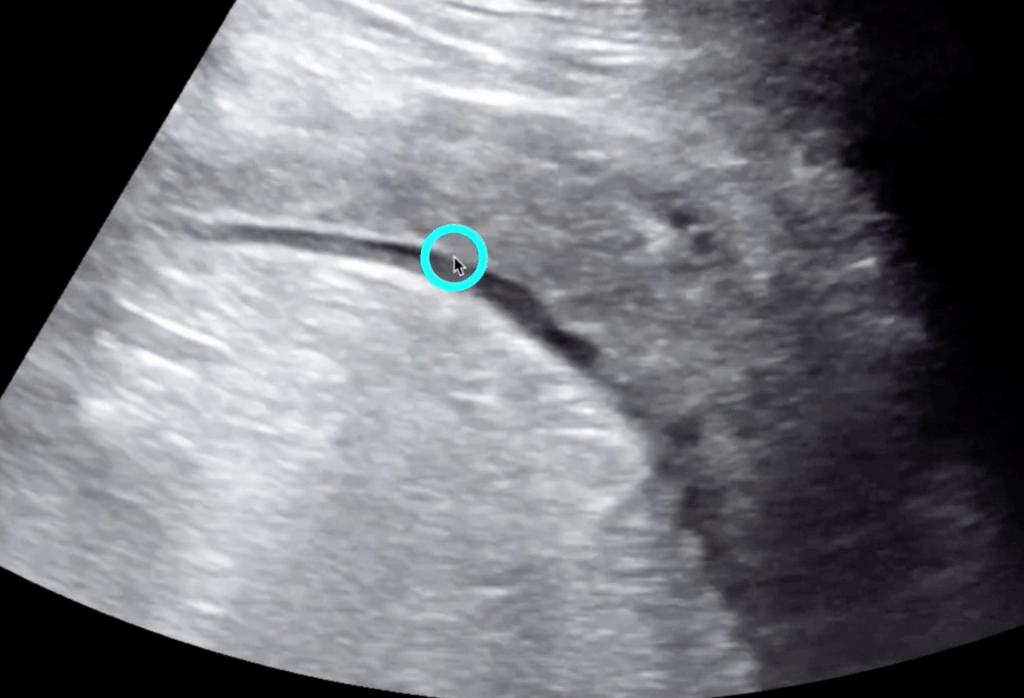

5 Minute Sono

- Large curvilinear probe

- Graded compression up and down

- Diverticula

- Bowel wall>5mm

- Prominent fluid-filled bowel loops

- Pericolic free fluid

- Increased pericolic fat (hyperechoic)

- Abscess